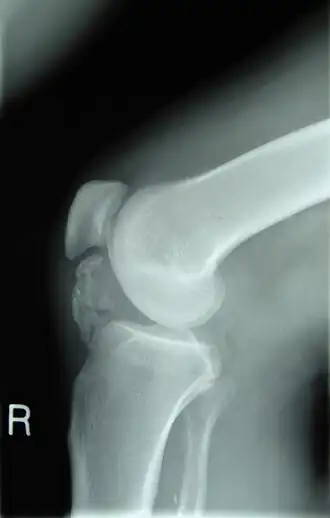

![]() Рентгенограмма колена пациента, больного остеохондромой. Видно окостенение околосухожильных тканей | |

Остеохондро́ма (лат. osteochondroma, множ. osteochondromata, костнохрящевой экзостоз) — доброкачественная опухоль кости, образующаяся из хрящевых клеток. Она представляет собой бесцветную массу, которая чаще всего образуется в возрасте от 10 до 25 лет на эпифизе длинной трубчатой кости, может также встречаться и в плоских костях.